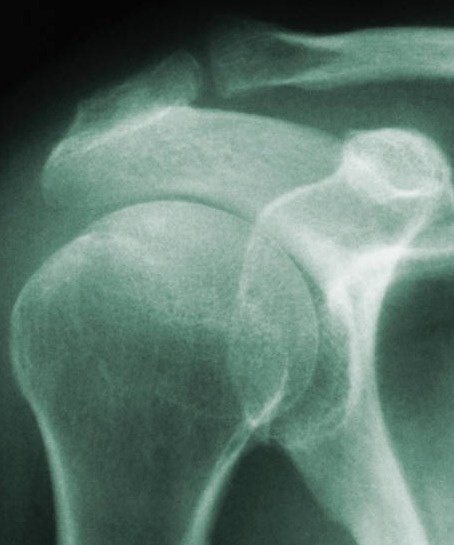

4 Common Causes of Shoulder Pain

2. Shoulder Arthritis

3. Rotator Cuff Problems